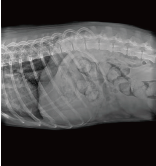

Application